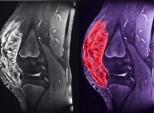

Ostéosarcome : un nouveau gène de prédisposition identifié

La mise en évidence d’altérations germinales du gène SMARCAL1 chez près de 2,6 % des enfants atteints d’ostéosarcome redessine le paysage du risque génétique. Ces données plaident pour un dépistage germinal plus large et des parcours de soins intégrant conseil génétique et surveillance ciblée.